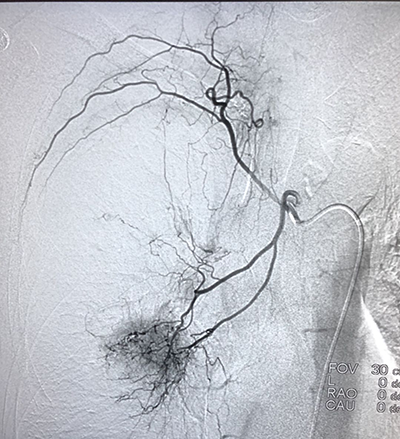

![]() | ![]() |

| (肺癌的介入治疗) | (盆腔恶性肿瘤的介入治疗) |